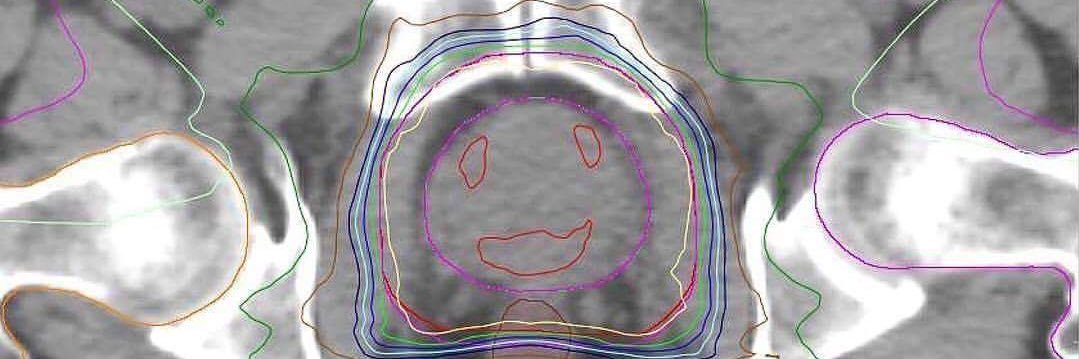

Radiotherapy–drug combinations need to move earlier in the development pipeline to truly maximise patient benefit. Check the new ESTRO Focus Group Policy Review. Read the full article: sciencedirect.com/science/articl…